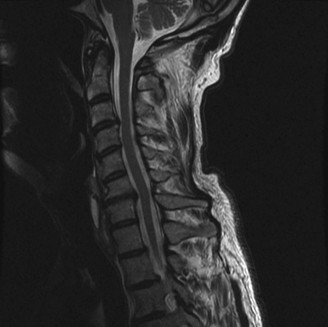

Radiographic and Computed Tomography Evaluation

Initial trauma radiographs demonstrated a loss of anterior and middle column height at L1, with a focal kyphotic deformity. However, plain films are vastly insufficient for definitive surgical planning in thoracolumbar trauma. A high-resolution, fine-cut Computed Tomography (CT) scan of the entire spine was obtained. The CT images confirmed an L1 burst fracture with severe comminution of the vertebral body. Sagittal and axial reconstructions revealed 50% canal compromise secondary to a large retropulsed bone fragment originating from the posterosuperior aspect of the L1 vertebral body. Furthermore, the CT demonstrated 25 degrees of segmental kyphosis measured from the superior endplate of T12 to the inferior endplate of L1.

Magnetic Resonance Imaging and the Posterior Ligamentous Complex

To definitively assess the integrity of the soft tissue stabilizers and the neural elements, a Magnetic Resonance Imaging (MRI) scan without contrast was performed. Historically, textbooks propagated the "50-50-25 rule," suggesting that a burst fracture was inherently unstable if it exhibited >50% canal compromise, >50% loss of vertebral body height, or >25 degrees of kyphosis. Modern spine trauma surgery has largely debunked this rigid radiographic dogma. We now understand that these bony metrics alone do not dictate mechanical instability. The true arbiter of stability is the Posterior Ligamentous Complex (PLC).

The MRI, particularly the Short Tau Inversion Recovery (STIR) and T2-weighted sagittal sequences, provided the definitive diagnosis. The images demonstrated profound hyperintensity and discontinuity of the ligamentum flavum, the interspinous ligaments, and the supraspinous ligaments at the T12-L1 level. The facet joint capsules were also disrupted, indicated by fluid within the joints. This complete failure of the PLC means the posterior tension band is gone. Regardless of the bony parameters, this spine cannot resist physiological flexion loads. If treated non-operatively, this injury will inevitably lead to progressive kyphosis, delayed neurological deficit, and intractable pain.